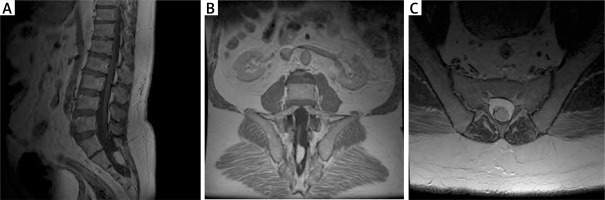

MRI (1.5 T) showed a thickened terminal strand with a low-lying spinal cone at the S2 level and an accompanying terminal strand fatoma, which argues for the first type of TCS (true TCS, Figure 4).

Figure 4

Preoperative MRI examination of the second patient. A – T1-weighted study showing end-strand adipose and end cone at L5-S1. B – T1-weighted study, coronary sections; visible ratio of the fatoma to the terminal strand. C – axial sections at T2 time; fat pad filling the vertebral canal with visible end thread